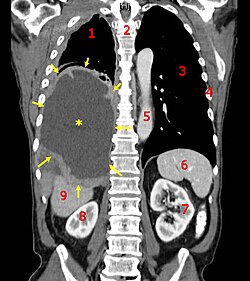

Kompyuter tomografiyasida koʻringan xavfli mezotelioma oʻsmasi.

Saraton mutatsiyaga uchragan hujayralarga qarab asosiy 4 guruhga boʻlinadi. Karsinoma — epitelial toʻqimalarda, sarkoma — mezenxemal toʻqimalarda, leykemiya — qon ishlab chiqaruvchi ilikda, limfoma va miyeloma — immunitet tizimi hujayralarida va bosh miya hujayralarida atipik rivojlanishni anglatadi. Tabiiyki saratonning „suyuq“ turlari oʻsma paydo qilmaydi.